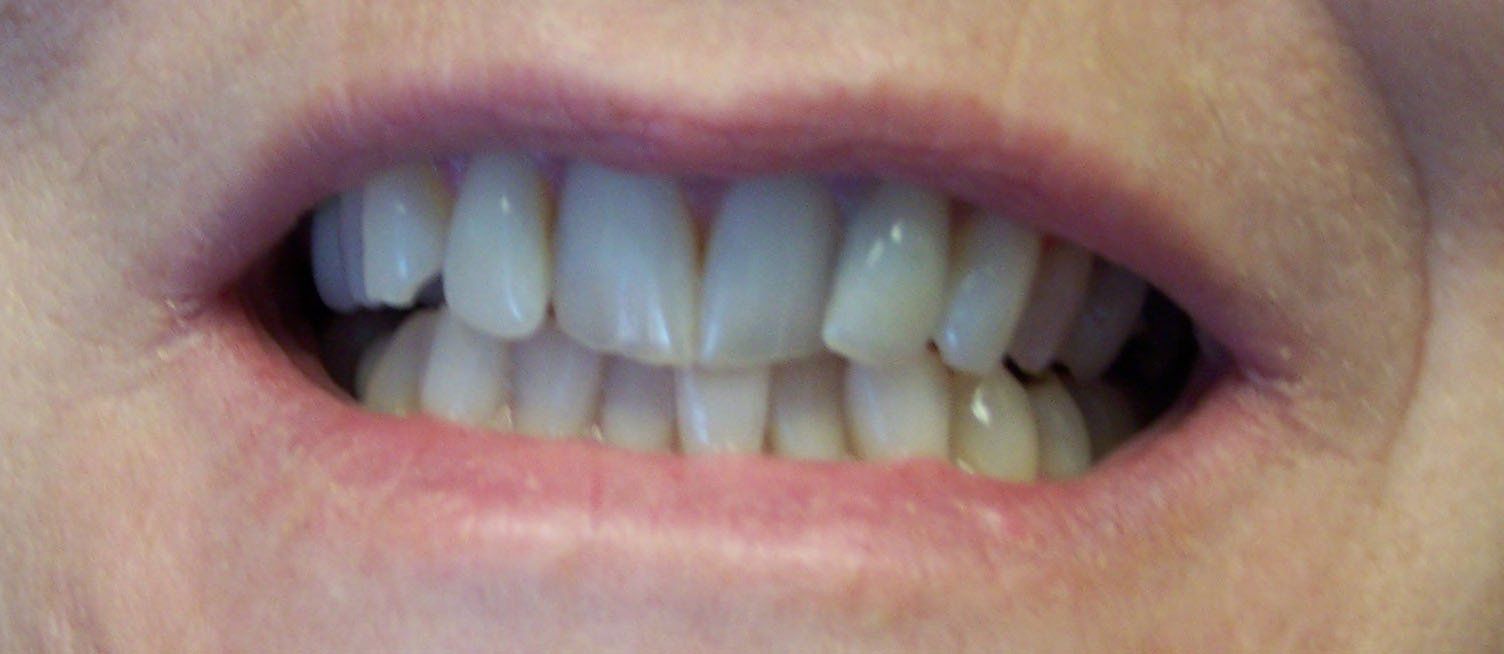

Ally Before

Button